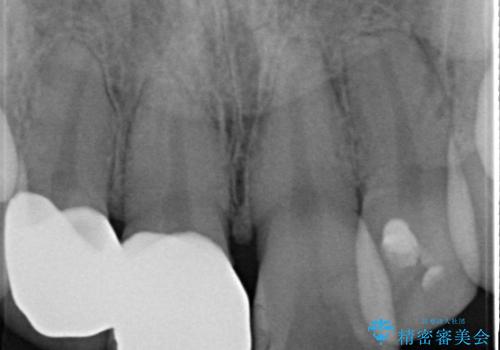

- 昔治療したプラスチックの材料が目立つから、セラミックで被せたいということを主訴で来院された患者様です。

虫歯治療をし、仮歯を制作し、オールセラミック(スタンダード)にて治療させていただきました。